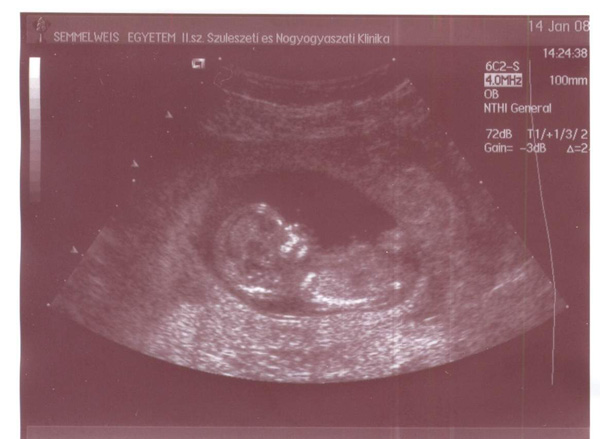

Én is úgy hallottam,hogy 30 ezer körül van a teszt ára és totál meglepődtem,hogy a mi kis szutyi vidéki kórházunk(amit mindenki szid)ilyen fejlődésbe kezdett.Van 4d-s uh gép is,csak sajnos idejük nincs az orvosoknak foglalkozni vele,mert annyi a kismama.Azért a 12 hetesen rendes volt a doki,mert adott képet grátiszba.Igaz,hogy alig látszik vmi,mert elbújtak,de a lelkemnek jól esett a törődés.Amúgy mindenki nagyon normális és mindent megtesznek a lehetőségeikhez képest.

Ha apa hazaér,megpróbálok uh képet feltenni.